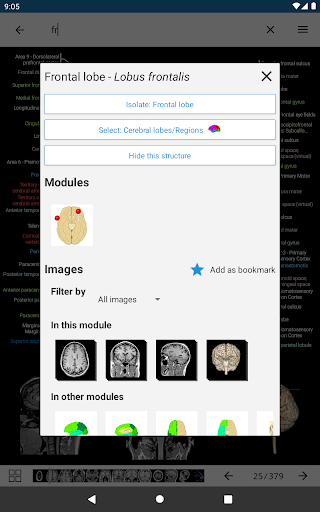

* تحسين عرض التفاصيل للأجزاء التشريحية لتسهيل التعرف عليها في صور الوحدات الحالية والوحدات الأخرى.

* اعثر على الأجزاء التشريحية الخاصة بك بسهولة أكبر بفضل ميزة البحث الجديدة والأكثر سهولة وقوة

* تحسين رؤية تعريفات الأجزاء التشريحية